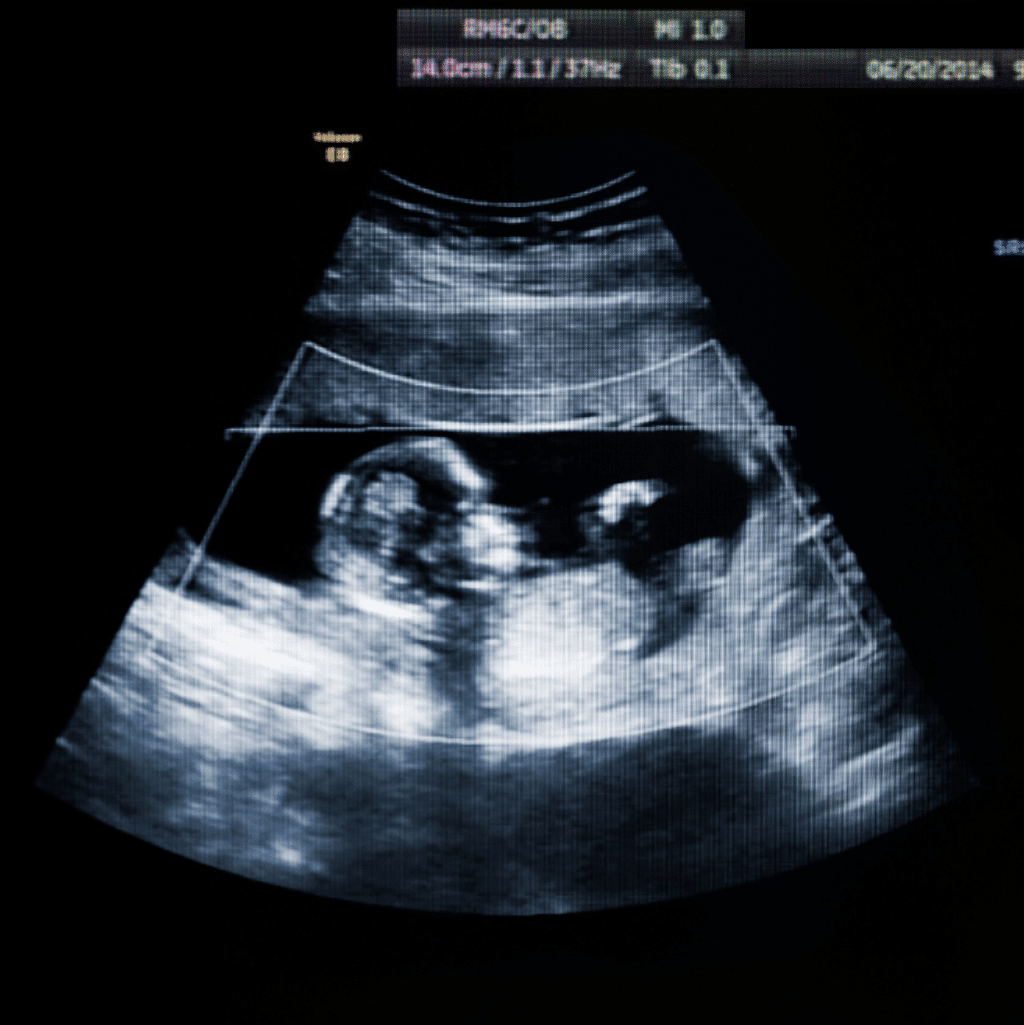

סקירת מערכות מאוחרת הינה בדיקת אולטרה-סאונד המבוצעת בשבועות 20-24 להריון.

הבדיקה מכונה גם "סקירת מערכות של הטרימסטר או השליש השני" והיא דומה באופייה לסקירת המערכות המוקדמת. משמע, מדובר בבדיקת אולטרה-סאונד, בלתי פולשנית וללא קרינה מייננת